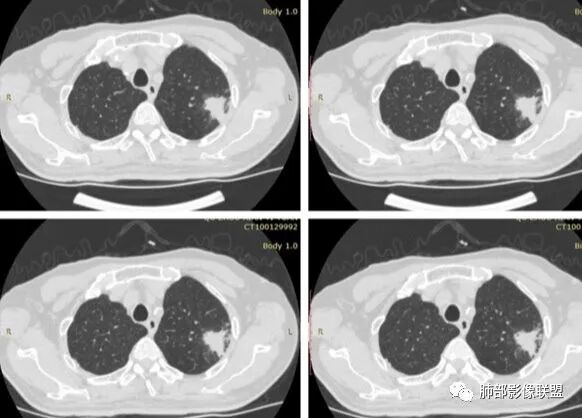

1、患者老年男性,无明显临床症状。

2、病灶位于左肺上叶尖后段,符合肺结核好发部位。

3、病灶密度不均,可见钙化点,未显示空洞或液化。边缘收缩,U型凹陷、桃尖征、细长毛刺以及较长棘状突起。宽基底与胸膜相连,邻近胸膜广泛性增厚(未见栽赃侵入)。可见卫星病灶,周围的磨玻璃影比较松散,炎性病变征象多,符合结核的CT表现。

4、部分区域膨隆,未见支气管截断,肺门纵隔未见肿大淋巴结等,恶性征象少。

5、结合其无临床症状、病灶形态、病灶位置及发病率,结核居多,最后诊断在大家意料之中。